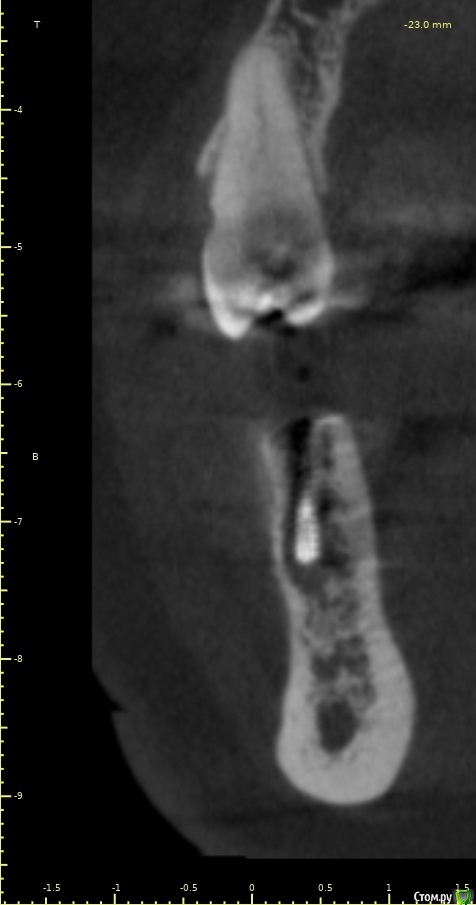

Женька Опубликовано 28 ноября, 2020 Поделиться Опубликовано 28 ноября, 2020 (изменено) Приветствую коллеги. В общем три недели назад 07.11.20 установил пациентке 2 имплантата в позиции 45-46. Гребень по ширине был около 6.5мм в области 4.5 и около 7.2мм в области 4.6 (с учётом заглубления на 1.5-2мм). Это была наверное первая имплантация во время которой я чувствовал себя спокойно и расслабленно. Всё прошло хорошо, немного покопался с непосредственным введением имплантатов, тк никак не хотели топиться на нужные 1.5мм. Поэтому пробовал методику с выкручиванием на пару витков и снова закручиванием. Особого толку не получил, потому взял финальную фрезу и чуть углублял ложе. Так несколько раз, тк боялся всё-таки немного что задену менталис и нлн. Ввиду того, что биотип у пациентки тончайший и язычно было совсем-совсем тонко - заглушки и швы. Назначил нпвс, ванны хг, аб терапию. Но на утро следующего дня пациентка сказала, что чувствует себя шикарно, решили что нпвс оставим, а аб терапию применять не будем (и грешу что в этом мою ошибка).Через неделю сняли швы, всё отлично.Спустя два дня после снятия начались какие-то "костные" боли, как говорит пациентка в области 4.5 импланта. Которые то отпускают, то снова наплывают. На 4.4 есть дефект твердых тканей (на фото виден), но судя по всему беспокоит не он .Пальпация вестибулярно в проекции 4.5 импланта болезненна, небольшая гиперемия, отёка нет. Гигиену пациентка запустила, тк боялась туда залезать и чистить. Снимки прилагаю первые два от 07.11, два последующих 28.11. Ну и внутри ротовые день операции и сегодняшние числа.Похоже 4.5 на выход? своими "туда-сюда" наверняка я нагрел всё что можно... снова расстройство в той работе, где накосячить предельно сложно... Добавка: пить аб ведь сейчас уже бесполезно? Изменено 28 ноября, 2020 пользователем Женька Ссылка на комментарий

Женька Опубликовано 14 декабря, 2020 Автор Поделиться Опубликовано 14 декабря, 2020 (изменено) Наконец-то получил КТ от пациентки...Боли значительно уменьшились, практически не беспокоит... Коллеги, что думаете? Я так понимаю это уже не фон от титана? и вердикт всё-таки один? Сам склоняюсь всё-таки более к понаблюдать. Вестибулярно конечно очень тонко Толщина была ~ 6.7мм Изменено 14 декабря, 2020 пользователем Женька Ссылка на комментарий

Irouil Опубликовано 14 декабря, 2020 Поделиться Опубликовано 14 декабря, 2020 Ну и где тут язычно передавленная кортикалка? Меня смущает только картина в области верхушки симптомного винта, ну и заглубление Я бы дождался уже срока интеграции Ссылка на комментарий

Женька Опубликовано 14 декабря, 2020 Автор Поделиться Опубликовано 14 декабря, 2020 Ну и где тут язычно передавленная кортикалка? Меня смущает только картина в области верхушки симптомного винта, ну и заглублениеНе знаю, я про язычную кортику не говорил. Меня тоже смущает... и в области соседа такого фона (а это не фон я уверен) нет... А с заглублением что не так? по прицелам там 1.5-2мм, на кт почему-то этих мм вообще нет и как будто крестально стоят Ссылка на комментарий